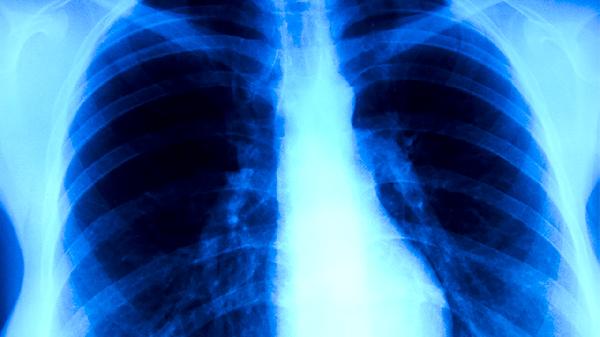

肺結核病是如何傳播的

肺結核病主要通過飛沫傳播、接觸傳播和母嬰傳播三種途徑傳染。肺結核病是由結核分枝桿菌引起的慢性傳染病,主要傳播方式有呼吸道飛沫傳播、密切接觸傳播、母嬰垂直傳播等?;颊呖人浴⒋?a href="http://www.phgsvzt.cn/k/dgiirmiqkreybb9.html" target="_blank">噴嚏或說話時產(chǎn)生的飛沫是主要傳染源,與患者長期密切接觸也可能導致感染,孕婦感染后可能通過胎盤或產(chǎn)道傳染給胎兒。

呼吸道飛沫傳播是肺結核最常見的傳播途徑。當肺結核患者咳嗽、打噴嚏或大聲說話時,會產(chǎn)生含有結核桿菌的飛沫核,這些飛沫核在空氣中懸浮,被健康人吸入后可能導致感染。飛沫傳播的風險與患者排菌量、接觸距離和環(huán)境通風情況有關。在密閉、通風不良的環(huán)境中,飛沫核可長時間懸浮,增加傳播概率。